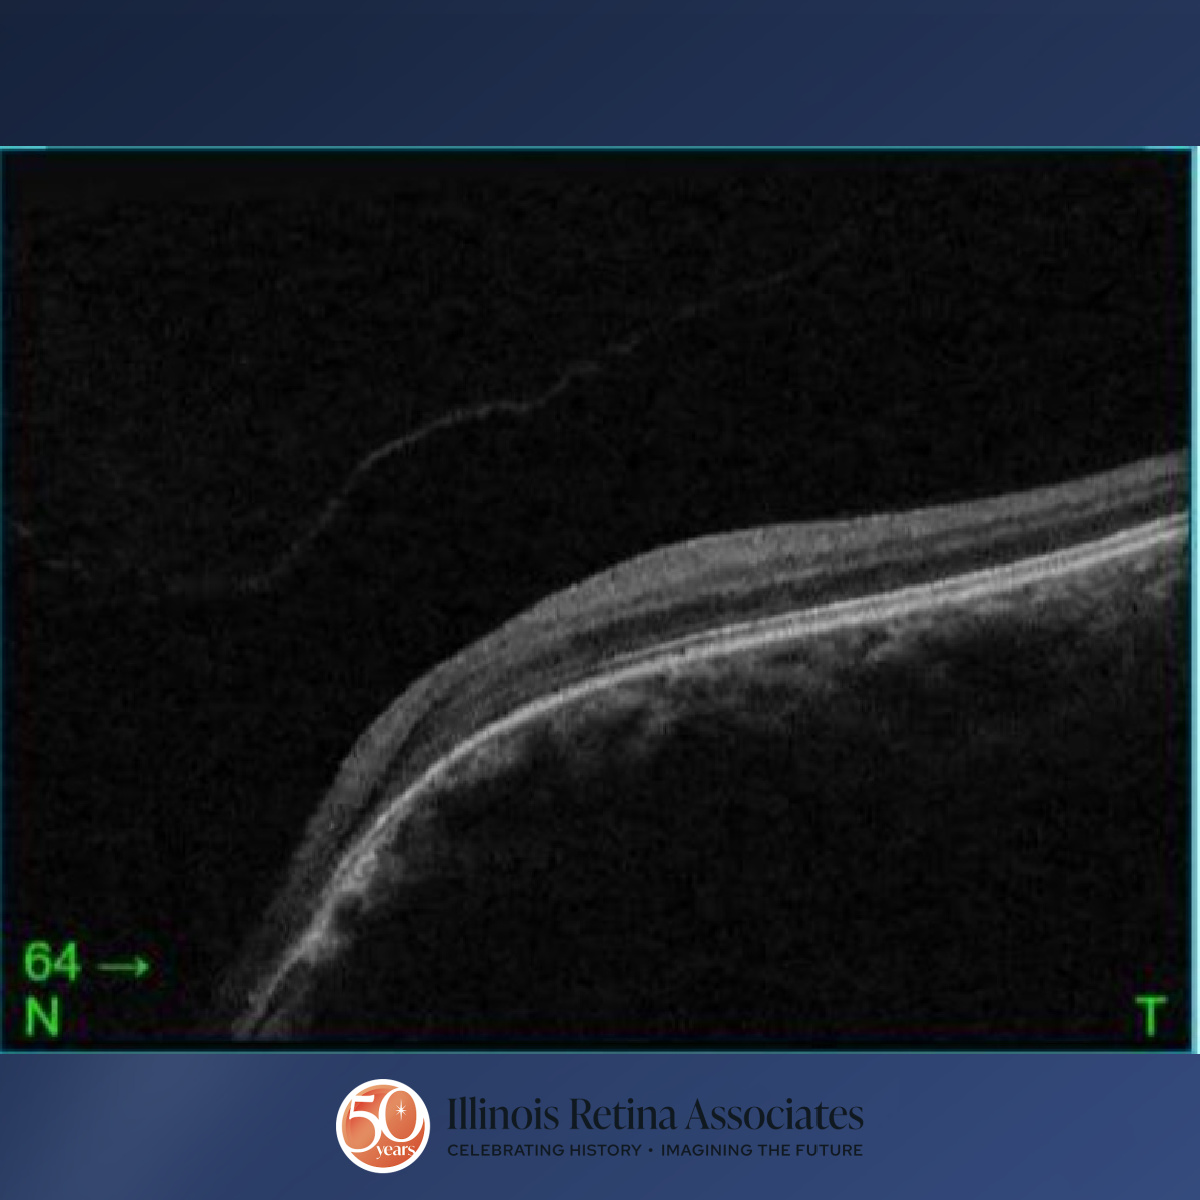

Visual acuity was 20/25 in the right eye (OD) and 20/40 OS. Intraocular pressures were within normal limits in both eyes (OU). Anterior segment exam was remarkable for persistent pupillary membranes bilaterally. Posterior segment exam OD demonstrated a cup to disc ratio of 0.5 and mild peripapillary atrophy (Fig 1) and OCT demonstrated vitreomacular adhesion (Fig 2). Posterior segment exam OS revealed a funnel-shaped optic nerve with a c/d ratio of 0.5, peripapillary atrophy and pigmentation, and straightened retinal blood vessels overlying the optic disc margin (Fig 3). OCT OS was significant for a nasal staphyloma (Fig 4). A previous MRI/MRA of the brain was normal.